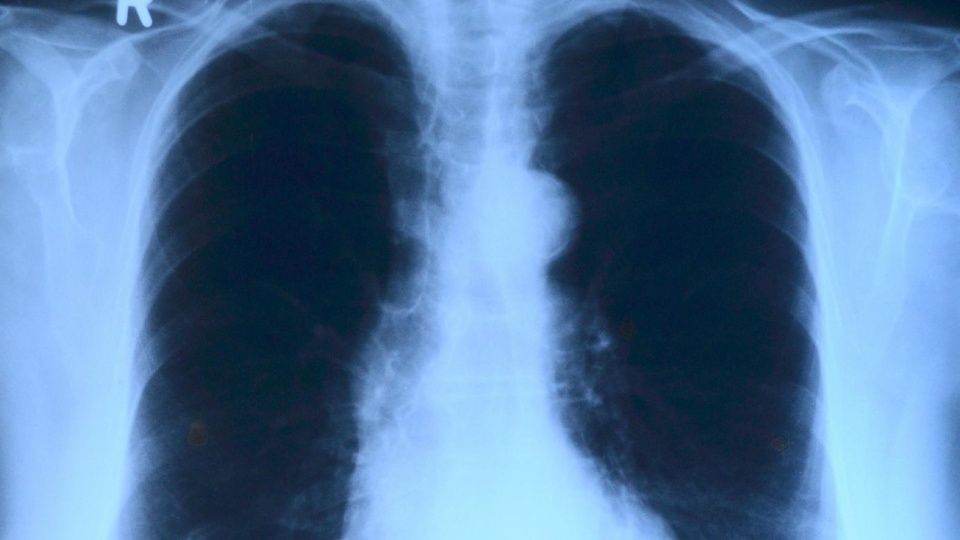

Quienes sufren de fibrosis quística padecen de una mucosidad que afecta sus pulmones y otras partes del cuerpo. Foto: Pixabay